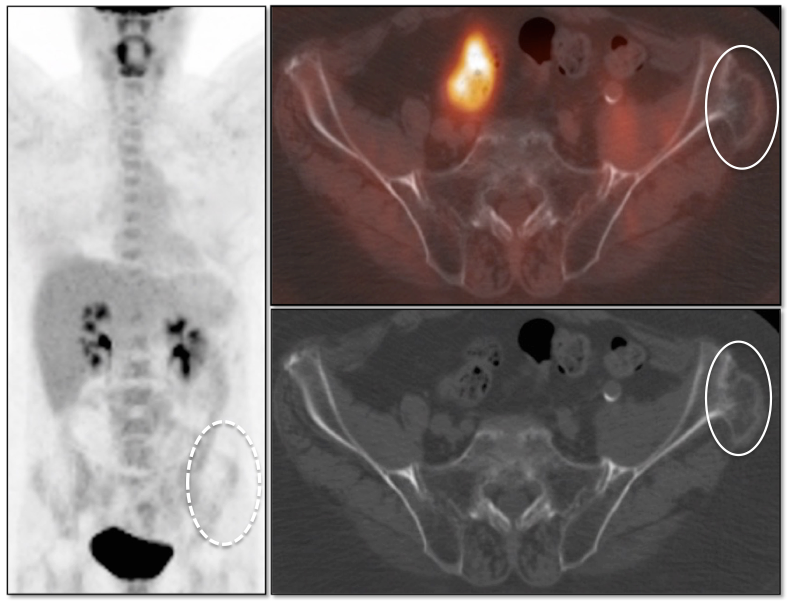

Schmorl’s Node:

A Schmorl’s node is a focal herniation of disc material into a vertebral body. It appears as a rounded lucency in the vertebral body, contiguous with its endplate. The lucency often demonstrates surrounding sclerosis.

While typically non-avid, Schmorl’s nodes can be FDG-avid, occasionally demonstrating even intense metabolic activity. MRI evaluation may occasionally be required to distinguish a hypermetabolic Schmorl’s node from a lytic metastasis.